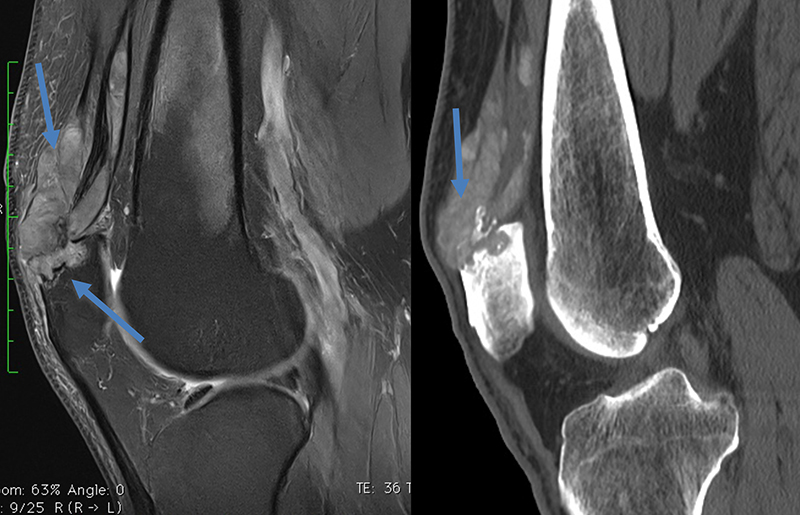

Fracture de Segond